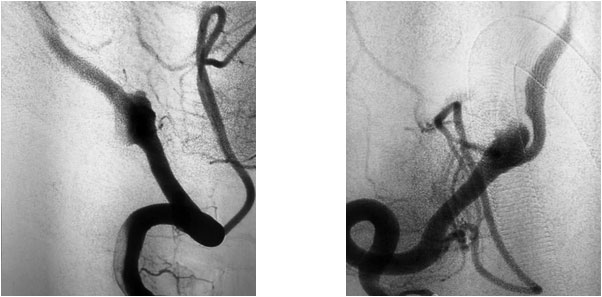

患者为65岁男性,20天前无明显诱因突然出现四肢无力,呈渐进性加重,以下肢为甚,伴头晕、头痛,呈一过性,在当地医院急查头颅CT示:右侧椎动脉V4段动脉瘤。当时症状自行缓解,未做处理。后患者自感症状间断发生,为求进一步治疗,遂转至上海蓝十字脑科医院。

患者既往有“高血压”病史8年,“糖尿病”病史1年余。头颅增强CTA示:右侧椎动脉V4段动脉瘤,直径7.5毫米,右侧颈内动脉C4-6段多发钙化斑块形成,伴相应管腔轻度狭窄,左侧颈内动脉C5-6段微钙化斑块形成,左侧椎动脉偏细。

张琪博士指出,患者动脉瘤虽未破裂但已压迫大脑周围神经,导致头晕、头痛及四肢无力等神经系统症状和体征,手术指征明显。

在充分准备后,张琪博士在刘春医生、周林华医生协助下为患者进行了支架辅助动脉瘤栓塞手术。填入弹簧圈后,再置入支架,完全释放后,造影显示动脉瘤无显影,支架覆盖良好,载瘤动脉通畅,撤出微导管输送系统,复查双侧椎动脉造影显示远端血流通畅。

▲ 术前影像